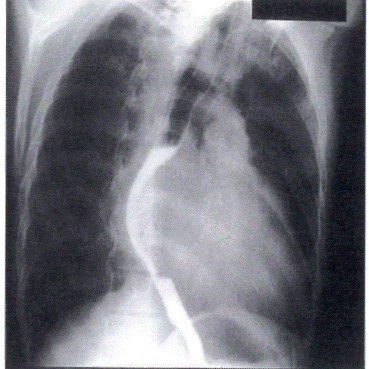

4. Диагностиканың ақ параттық ә дістерін, ЭхоКГ, ЭКГ, кеуде қ уысы ағ заларының рентгенографиясын интерпретациялауды білу

Р-грамманы интерпретациялау 2, 0 1, 0